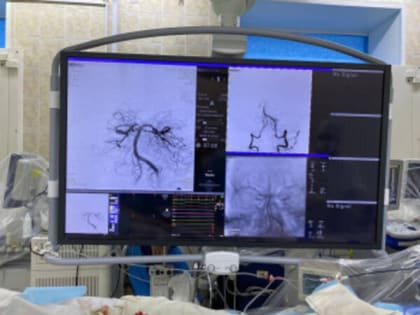

Результат томографии. Источник: Минздрав Оренбургской области В Оренбурге хирурги провели операцию под названием «Реканализация, аспирационная тромбэкстракция (удаление тромбов) из базилярной артерии» пациенту,

В Оренбурге рентген-хирурги Алексей Демин и Эдуард Гаврилов удалили 59-летнему пациенту тромб в базилярной артерии мозга.

Рентгенхирурги областной клинической больницы имени Войнова впервые в регионе выполнили операцию по удалению тромбов из базилярной артерии, снабжающей кровью задние отделы мозга.